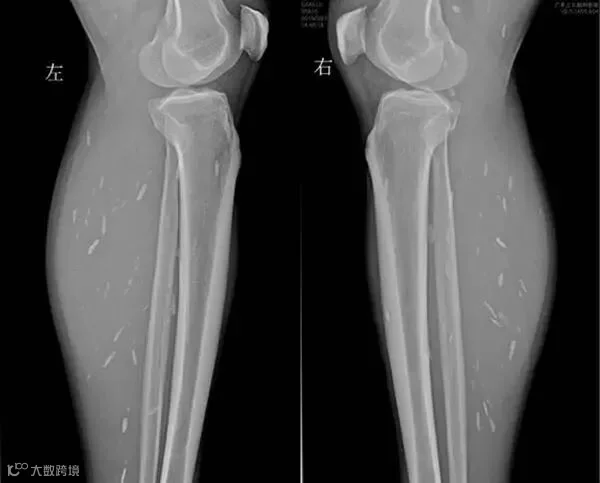

令人吃惊的是

除了头部,影像检查还提示

患者双下肢也有囊虫

分散密布在左小腿和右小腿处

▼